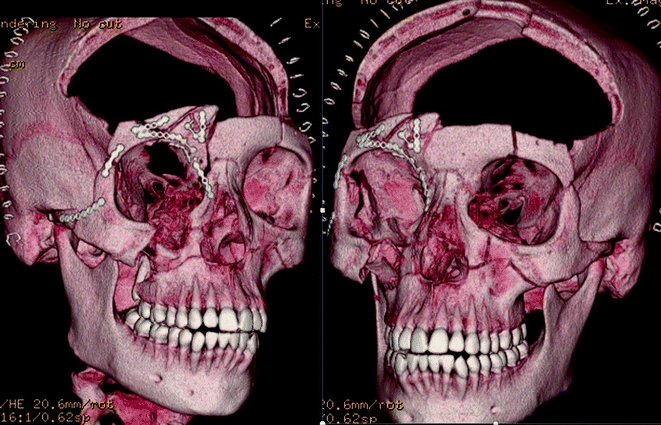

Fig. 19.10

Three-dimensional reconstruction showing complex cranial, facial, and orbital fractures

Fig. 19.11

Three-dimensional reconstruction showing complex cranial, facial and orbital fractures